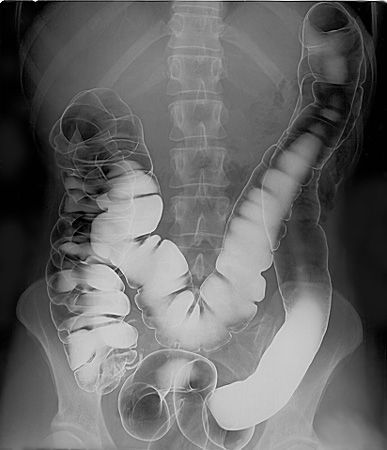

Double contrast barium enema (DCBE) technique is a fluoroscopy procedure for the imaging of colon. It is called double contrast because the imaging is done with the help of two contrasts, one positive contrast (e.g. barium sulfate contrast) and one negative contrast of gas (preferably CO2). This imaging procedure is indicated and takes preference over single contrast technique in cases where better visualisation of the mucosa is required. In the past this technique had been used for colon cancer screening too. Text Reference: https://radiopaedia.org/articles/double-contrast-barium-enema-technique Image Source: https://en.wikipedia.org/wiki/Double-contrast_barium_enema#/media/File:Human_intestinal_tract,_as_imaged_via_double-contrast_barium_enema.jpg